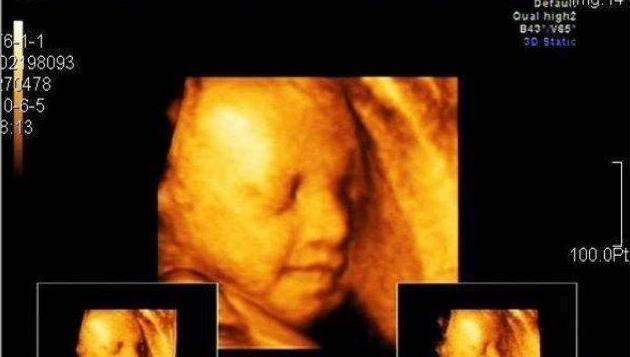

孕期准妈一般都会进行四维彩超的检查,更好更全面的认识宝宝,虽然说每个地区的价格有所偏差,但是整体来看四维彩超价格还是挺高的。贵自然有它贵的道理,而准妈要做的是让检查“物超所值”。

有的准妈妈做四维的时候,会遇到胎宝宝不配合,在医院浪费了大把时间,也无法看到宝宝活泼可爱的一面。准妈妈要注意四维不用空腹,准妈饿着胎宝宝,宝宝哪有精神力气来配合准妈妈做检查呢?吃饱喝足,让宝宝元气满满。

准妈妈也可以随身携带几块巧克力,要是遇到“懒”宝宝,可以十几块巧克力,唤醒宝宝的活力,当然,有的医生也会建议准妈出去转转或者爬爬楼梯,让宝宝一起动起来。准妈妈也要保持一个良好的情绪,不要太紧张,不然也会影响到检查的结果。

准妈做检查的时候穿着也要宽松舒适,不要穿连体衣,最好是裤子和上衣分开,这样方便做检查。四维彩超有点小贵,准妈要全面了解四维,才不会遇到宝宝不配合,自己受累,可能也会影响到检查的结果,可能又要多做几次,又要另外花钱。